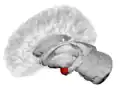

Coronal section of brain through intermediate mass of third ventricle. Amygdala is shown in purple.

The medial nucleus is involved in the sense of smell and pheromone-processing. It receives input from the olfactory bulb and olfactory cortex.[29] The lateral amygdalae, which send impulses to the rest of the basolateral complexes and to the centromedial nuclei, receive input from the sensory systems. The centromedial nuclei are the main outputs for the basolateral complexes, and are involved in emotional arousal in rats and cats.[6][7][30]